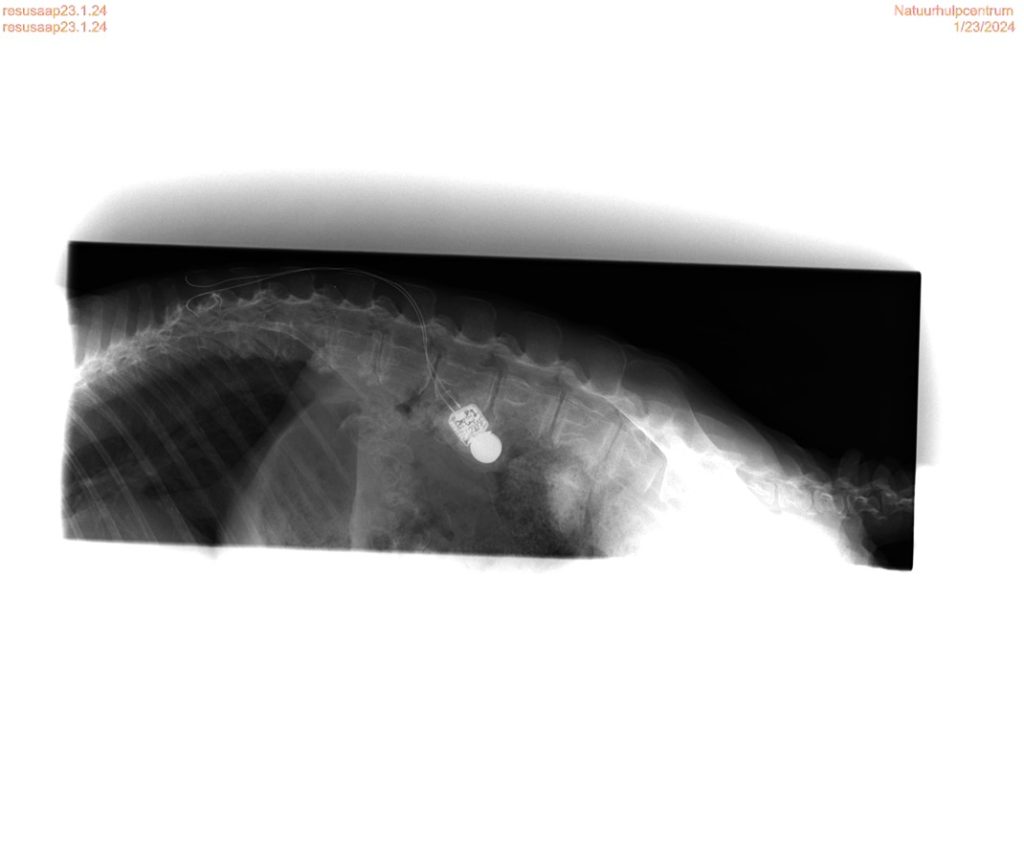

Rhesus apen Orion er en av de få dyrene som har fått lov til å bli boende på senteret. «Vi spurte myndighetene som lov til å beholde han her på senteret, for han er så sosial og trenger å se mennesker. Vi vet ikke helt hva slags forhold han kommer fra, men han har vært et forsøksdyr. Han er gammel og har artrose, så vi måtte legge han i bedøvelse for å ta røntgenbilder. Da oppdaget vi at han har noe som ser ut som en nervestimulerings maskin inni kroppen sin, men vi vet ikke hva slags forskning han er blitt utnyttet til» forteller Frederik.